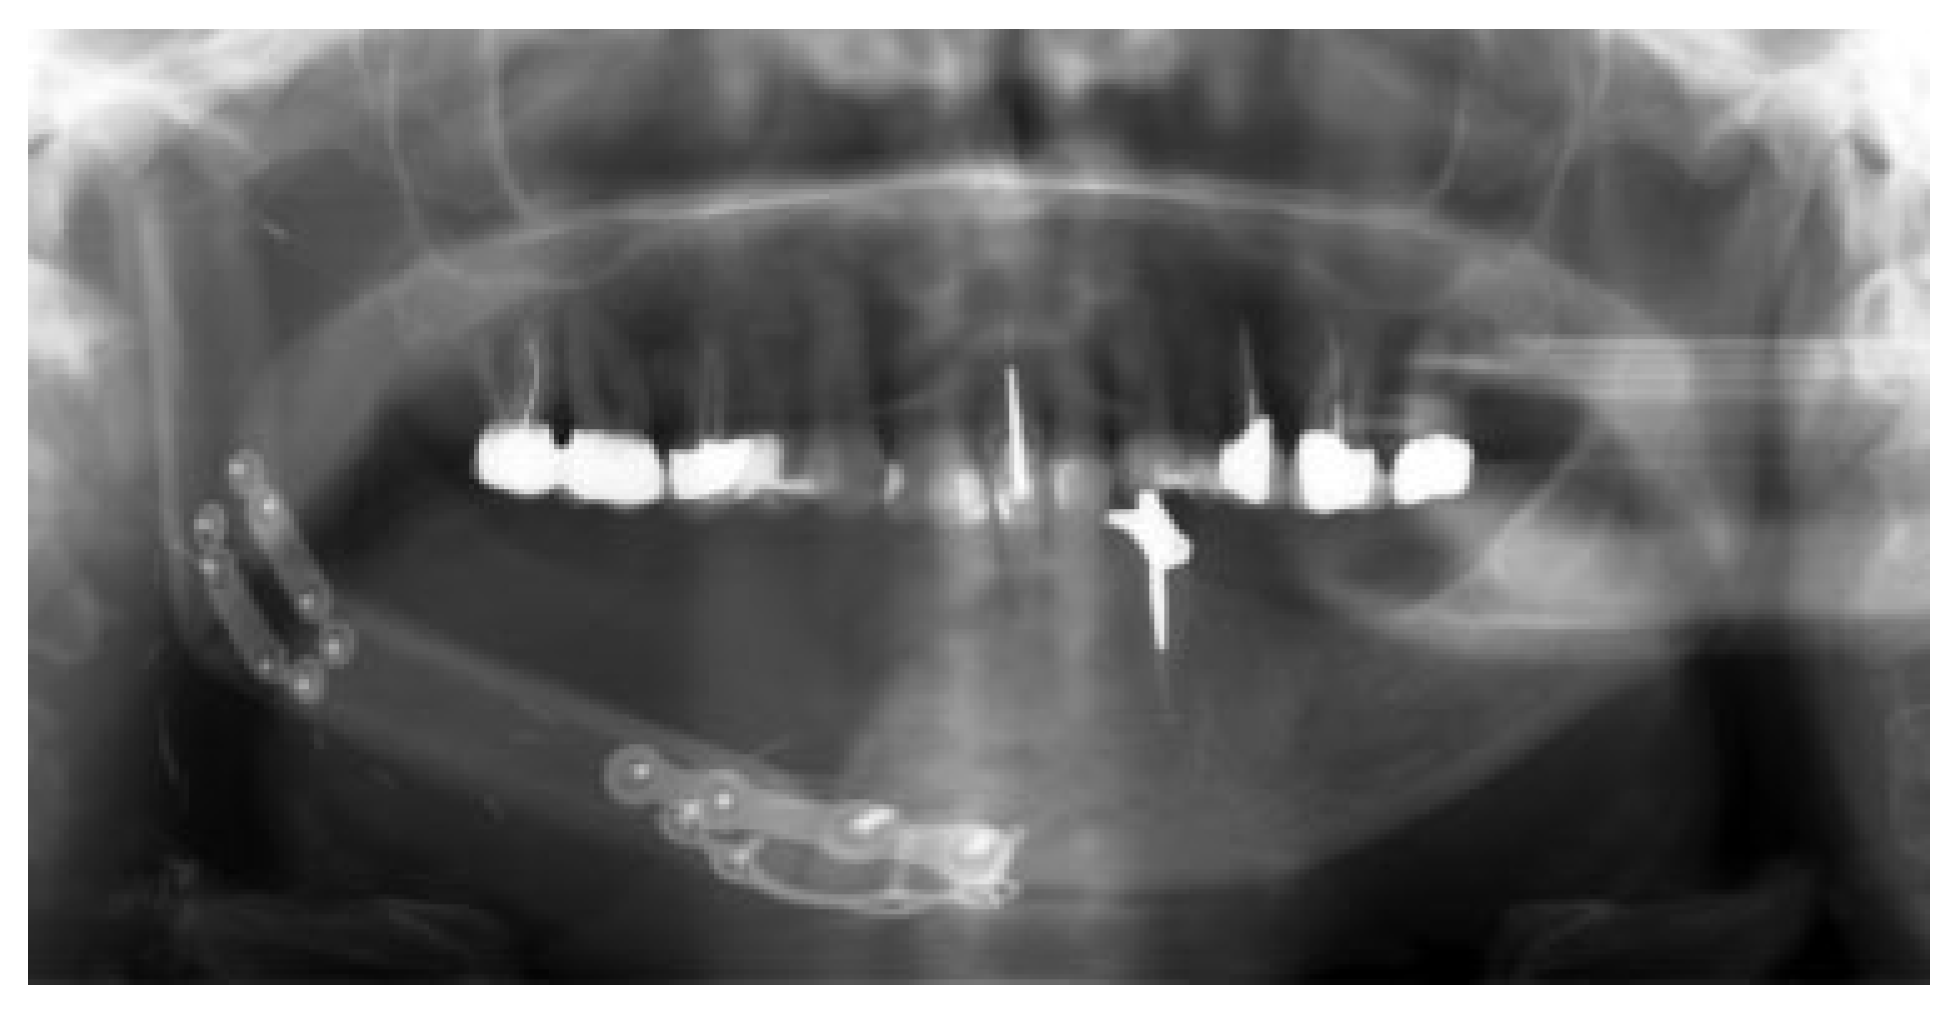

In 15 patients, 14 ablative surgical interventions were recorded, with 14 receiving primary or secondary reconstructive procedures; in one patient, no reconstructive procedure was performed due to a compounding medical condition (Table 2). This patient was excluded from further analysis due to lack of reconstruction. Eight patients had primary head and neck cancer, but in only four patients the condyle was involved due to infiltration, while four suffered from ORN. One patient suffered from a rare benign tenosynovial giant cell tumor. Two patients suffered from extensive osteomyelitis, and bisphosphonate osteonecrosis afflicted two patients. One patient had to be operated on twice due to hypertrophic bone formation around the metal condylar head and represents the only major complication in our series. She suffered facial nerve damage during the second surgery in a postradiated field, with the facial nerve lying on the reconstruction plate used in the first surgery (Figure 1). Six of the fourteen reconstruction surgeries took place in a radiated field, explaining the two plate exposures in an unrelated area, away from the condylar reconstruction. Two patients received total joint reconstructions combined with one and in the other two free flaps. Five patients received fibula flaps alone and one received a vascularized costochondral graft, while all of the others had metal condylar prostheses with or without a free flap (Figure 2, Figure 3 and Figure 4). Follow-up ranged from 2 to 84 months with an average of 30 months. In total, five patients suffered from complications that could be considered acceptable, as they all could be corrected with minor revision surgery or occlusal adjustment. One patient suffered from facial nerve damage after a reconstruction plate in which metal condyle had to be removed in a radiate. In 11 patients, reliable information was obtained regarding mouth opening of which 9 showed a marked improvement of more than 5 mm. Three patients had a decrease in mouth opening, but all could be regarded as functional as no mouth opening of less than 30 mm was recorded (Figure 4).

Figure 1.

Hypertrophic bone around metal condylar replacement.

Figure 2.

Osteoradionecrosis of the right mandible.